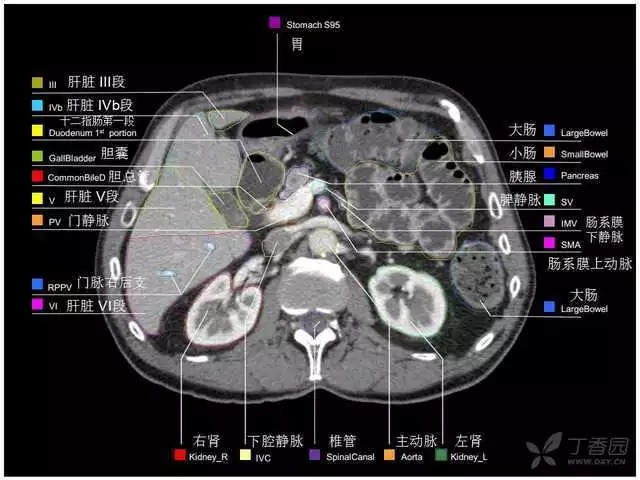

腹部肝脏高清CT断层的图谱

全腹部高清CT图谱,淋巴结彩色图谱,血管解剖图谱大汇总!

超声肝脏分叶及分段

肝脏分段和基本解剖学标志